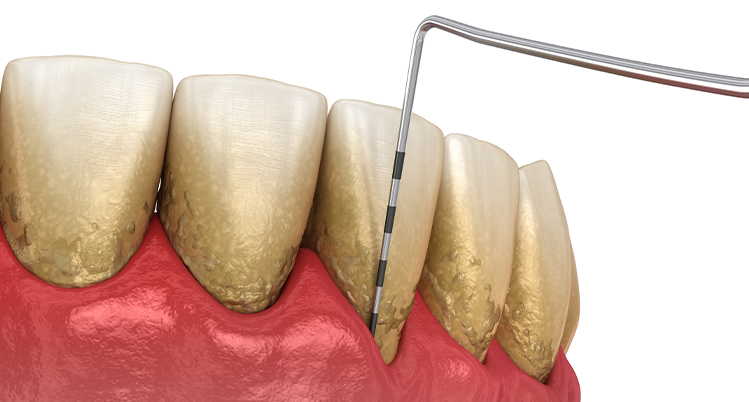

精密歯周病検査について

精密歯周病検査とは、現段階の歯周病レベルを判断するために行う検査です。

1. 歯周ポケットの深さを測定

専用の器具を使って歯ぐきの深さを測る検査です。定期健診などで行っている歯ぐきの検査と同じです。歯ぐきの深さを測るため少しチクチクと痛みを感じる方もいます。

1本の歯につき4~6か所測定します。

- 0~3mm 正常、歯肉炎、または軽度

- 4~6mm 中等度歯周炎

- 7mm以上 重度歯周炎

2. スケーリング(歯石除去)

歯科医院で行うクリーニングの中に含まれるもので、専用の機械や器具を使用して歯石を取り除きます。

歯石の表面にはざらつきがあり、プラークが溜まりやすくなるため定期的に除去しましょう。

3. SRP

(スケーリング・ルートプレーニング)

専用の器具を使って、歯ぐきの中にある汚れを除去して、歯の根っこ部分の表面を汚れの付着が起こりにくい状態に仕上げる処置です。

主に、歯ぐきの中にまで歯石が入り込んでいる中等度以上の患者さまに対して行います。痛みが強い場合は、麻酔をして行うこともあります。